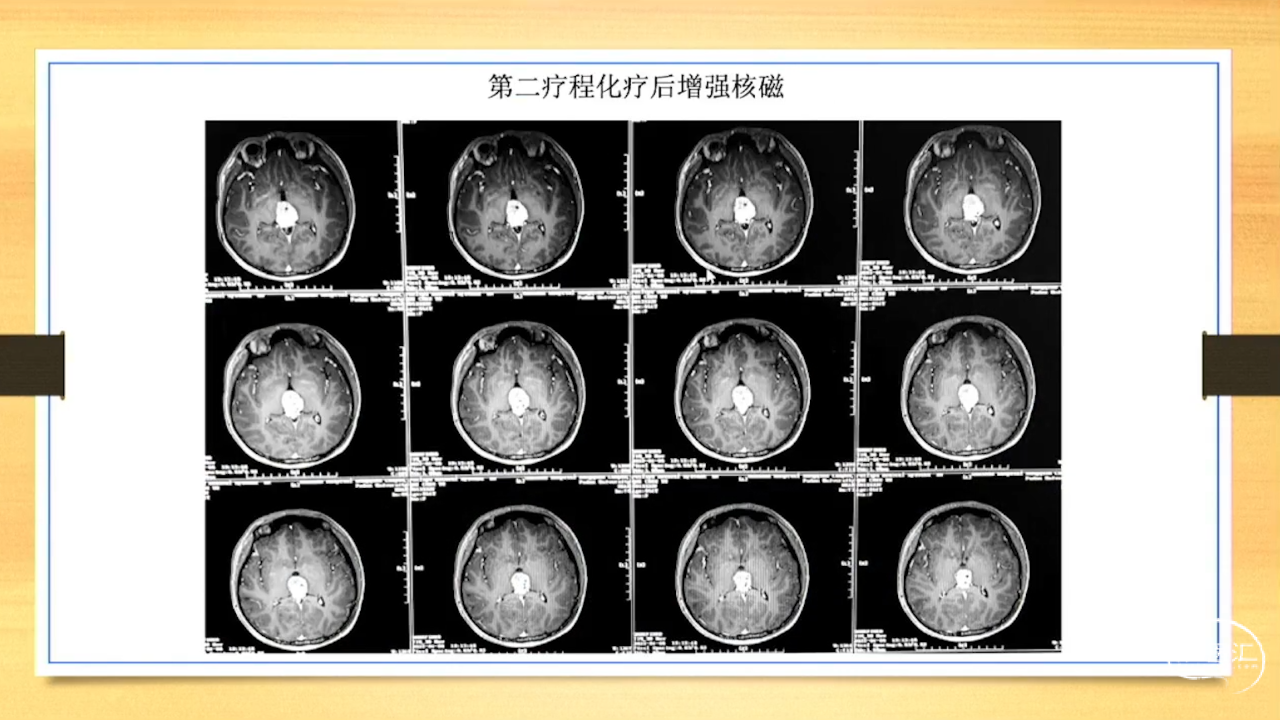

张荣教授:儿童颅内生殖细胞瘤的手术治疗

颅内生殖细胞肿瘤的治疗是手术、放疗、化疗、内分泌及其他多学科的整合治疗。及时、精准、合理的手术治疗是iGCT患者提高生存率、降低并发症、改善神经内分泌功能的关键。